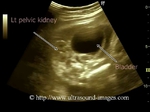

fetal-pelvic-kidney

This second trimester pregnancy shows the normal right kidney located in the right renal fossa. The Fetal left kidney was not visualised in the left renal fossa. However, a scan below the left lumbar region of the fetus, and into the pelvis reveals a hyper distended urinary bladder with the left kidney located just to the left of the urinary bladder. The ultrasound images above show one of the commonest anomalies involving renal ectopia, namely, pelvic kidney. A pelvic kidney though one of the commonest renal anomalies, must however, trigger a detailed examination of the fetus for other congenital anomalies involving the renal, genital, cardiac and skeletal systems. Pelvic kidneys may be bilateral and are often associated with undescended testes and hypospadias. these images of pelvic kidney are courtesy of Sunil Yadav, MD.